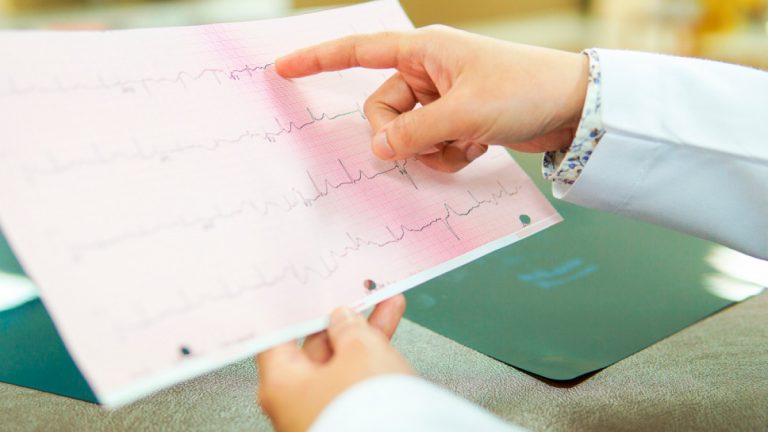

Te ofrecemos también la realización de Electrocardiogramas interpretado por médicos cardiólogos con basta experiencia